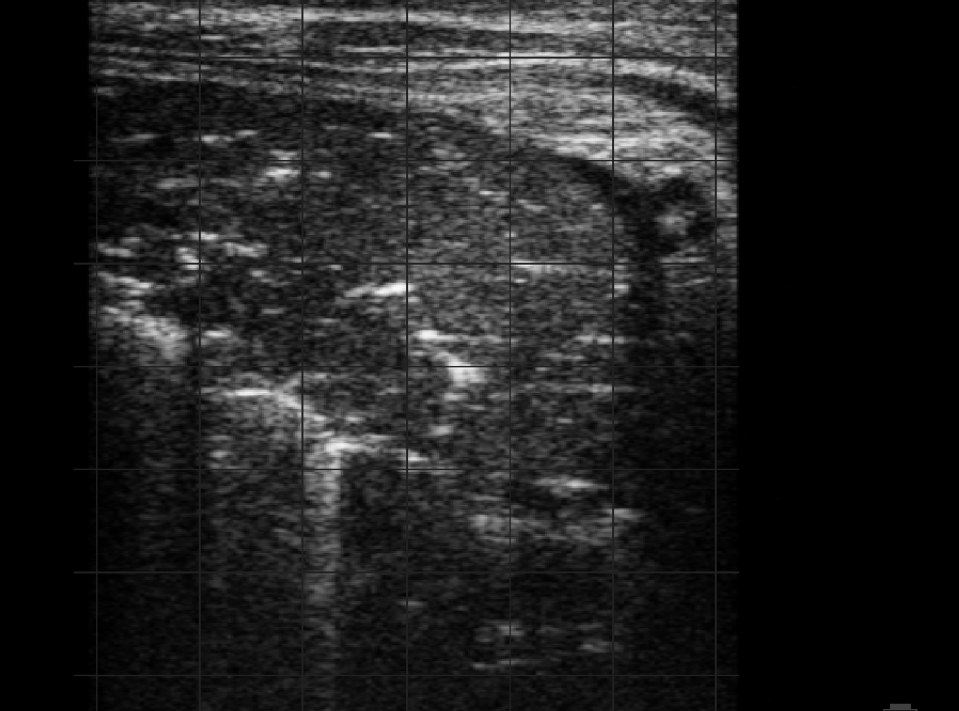

Ultrasonografické vyšetření může pomoci detekovat léze vznikající v plicích, bohužel i tak může být poškození, které BRD způsobí, nevratné. Komplikace zahrnují vznik trombů v plicní tkáni, což u skotu zanechává trvalé následky.

Ultrasonografické vyšetření může odhalit následující časné plicní anomálie spojené s pneumonií:

Zesílení/nepravidelnost pleurální linie:

Lze jej pozorovat ve formě B linií, což je řada hyperechogenních paralelních linií vznikajících v důsledku reverberačních artefaktů spojených s malými reflexními ploškami v pleurálním prostoru. Léze lze pozorovat také v případě plicního edému a difúzních parenchymatózních onemocnění.

Pleurální anomálie:

Vyznačují se ventrální akumulací různého množství hypoechogenní až anechogenní tekutiny s proměnlivým množstvím echogenních fibrinových vláken.

Lobulární nebo lobární léze:

Mohou být známkou zánětu a ukládání exsudátu v plicním parenchymu. Typickou izolovanou lobulární lézí je malá oblast konsolidace v jinak vdušném plicním laloku.

Abscesy:

Zanícená plicní tkáň, která obsahuje hnis.